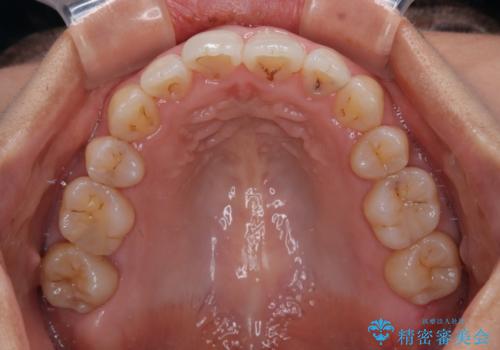

- 前歯のデコボコを治したいとのことで来院された患者様です。

上下顎ともに歯列全体の後方移動とIPR(歯と歯の間を削る)によってデコボコが解消するように設計し、インビザラインにより治療を行うこととしました。